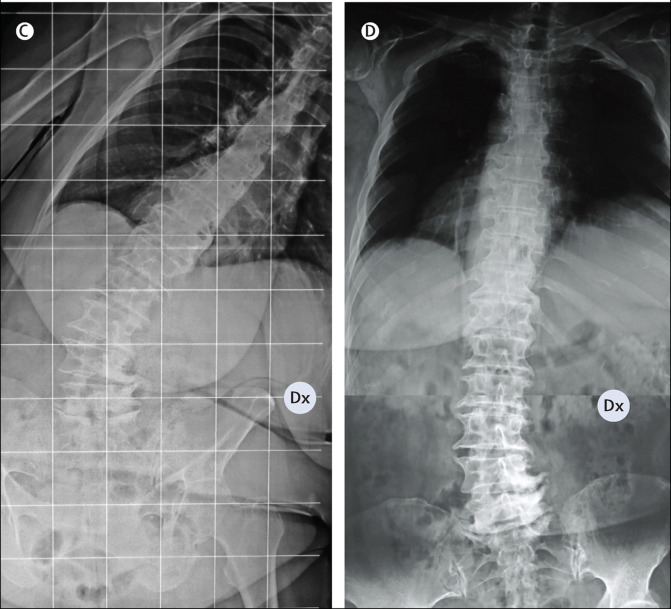

Симптом ригидного человека

Симптом ригидного человека 114 фото